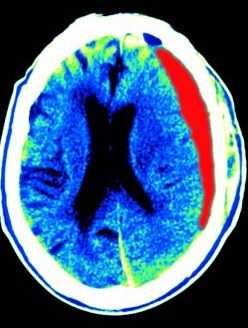

МРТ головного мозга. Т1-взвешенная аксиальная МРТ. Субдуральная гематома. Цветовая обработка изображения.

Субдуральная гематома обычно возникает вследствие разрыва вен. Причины субдуральной гематомы - травма, антикоагулянтная терапия, резкая декомпрессия при шунтировании желудочков по поводу гидроцефалии. Очень редко встречаются субдуральные гематомы при разрыве аневризм и АВМ. Клинические проявления связаны смасс-эффектом. Частота субдуральных гематом составляет около 1 случая на 10 тысяч населения. Располагаются субдуральные гематомы по конвекситальной поверхности, изредка, вдоль межполушарной щели и намёта, в области задней черепной ямки. Может быть сочетание субдуральной гематомы с кровоизлиянием в соседние участки мозга. прогноз в этих случаях неблагоприятный. Отображение гематомы на КТ и МРТ зависит от их давности. Субдуральные гематомы имеют форму серпа.